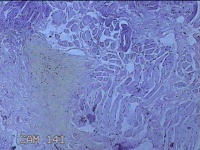

性别

男

年龄

26岁

临床诊断

皮脂腺囊肿

一般病史

发现前额部结节3年余。

标本名称

前额部结节

大体所见

灰白暗红色结节0.8x0.7x0.2cm一个,表面糜烂。

图4